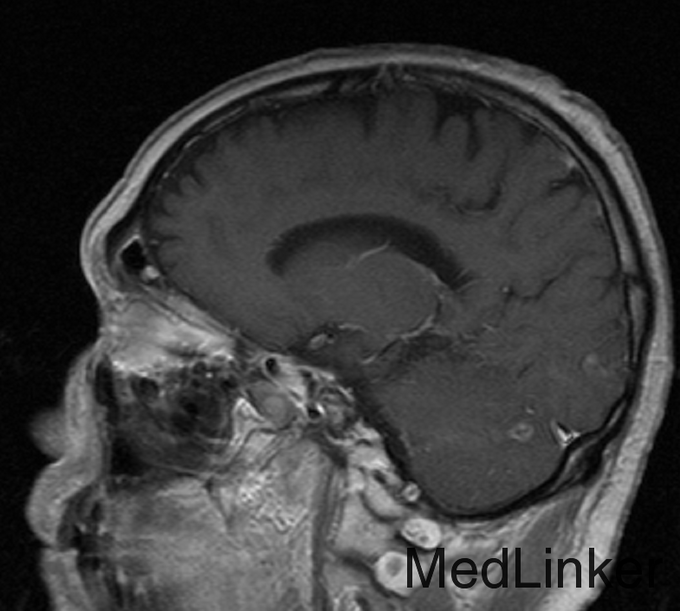

患者,男,56岁,因“右肺腺癌术后3年半余,头痛半年”入院。患者3.5年余前因肺癌在当地医院行手术治疗,术后予化疗8次,放疗32次,2年余前复查胸部CT见两肺转移。6月前患者出现头痛,不剧可忍,无视力模糊。

初步诊断:1.颅内转移性肿瘤 2.右肺腺癌术后,两肺转移。入院后完善相关检查:(2015-10-01 18:34)(急诊)血常规(血液):白细胞计数16.6×10^9/L↑、中性粒细胞百分比95.4%↑、(2015-10-01 19:19)(急诊)降钙素原(血液):C-反应蛋白217.5mg/L↑、癌胚抗原248.9ng/mL↑、癌抗原199354.0U/mL↑、癌抗原12556.0U/mL↑、癌抗原24277.8U/mL↑,(2015-10-05 14:04)行CT(胸部)检查提示:肺癌术后改变,两肺多发结节,考虑转移,较前(2014.05.05)增大、增多。入院后予邦达抗感染、甲泼尼龙40mg bid静滴减轻炎症反应,冸托拉唑40mg qd护胃,奥拉西坦4g qd修复脑神经,经治疗后患者病情好转,目前病情稳定,今予出院。